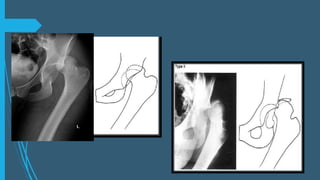

LUXACIÓN ANTERIOR

 Constituyen el 10-15% de los casos

Tipo I : Superior o púbicas (Riesgo de lesión del

paquete neurovascular femoral)

Tipo II: Inferiores incluyendo la lux. Obturatriz y

perineal.

IA: Sin fx asociada IIA: Sin fx asociada

IB:Con fx asociada de la cabeza o cuello femoral IIB: Con fx asociada de la cabeza o el cuello

femoral

IC: Con fx asociada del acetábulo IIIC: con fx asociada del acetábulo

Tipo 1

Tipo 2

Tipo IIA

TIPO IIB

TIPO IIC

Luxación de cadera anterior, central y posterior

LUXACIÓN ANTERIOR  Constituyenel 10-15% de los casos Tipo I : Superior o púbicas (Riesgo de lesión del paquete neurovascular femoral) Tipo II: Inferiores incluyendo la lux. Obturatriz y perineal. IA: Sin fx asociada IIA: Sin fx asociada IB:Con fx asociada de la cabeza o cuello femoral IIB: Con fx asociada de la cabeza o el cuello femoral IC: Con fx asociada del acetábulo IIIC: con fx asociada del acetábulo